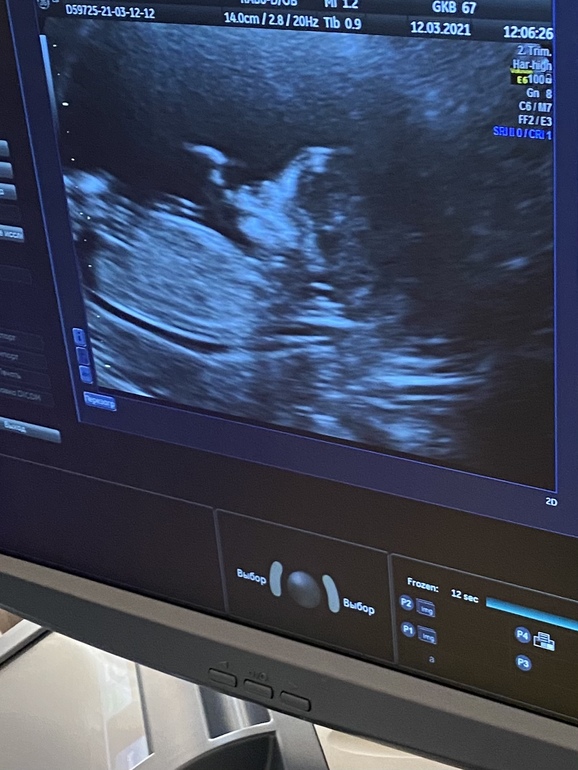

По узи все хорошо, малыш активный был вертелся, махал ручками и ножками, по размерам опережает срок на 5 дней (по м 12.4, узи 13.2). Первый раз включили сердечко, это счастье 😍

Фото не очень хорошее, но самое лучшее для меня